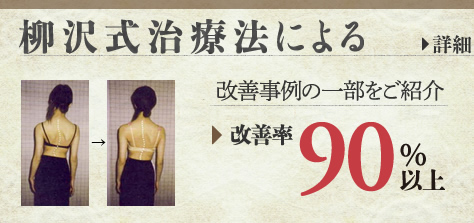

運よく機能性の側弯症であった場合(結構多いです)ほぼ治ります。(病院ではこの場合も「絶対治らない」と言われます。)突発性側弯症であった場合、完治は無理でも、高い確率で改善して差し上げることができます。